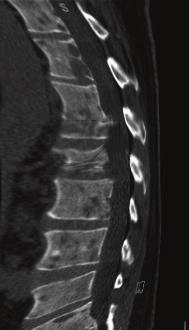

The tests were repeated for the patient again, general and comprehensive blood tests were performed and all agreed to a high levels of adrenal hormones in blood , radiographic images were also done in addition to magnetic resonance images throughout the body, the result of the tests and imaging was for the brain CT scan showed that there was no focal brain lesion and it was a metastatic spread test only, and no shift of midline structure and normal ventricular system, as the lumber spine CT showed that the findings were evidence of multiple bony lytic lesions seen in the lumber spine and sacral bone and no evidence of disc herniation or nerve root compression as showed in figure (7 ), this all tells that all back pains suffered by the patient were due to the presence of the tumor only .

The pelvic MRI showed that there were multiple hyper intense signals seen in the left ischium, that suggested bone metastasis while the abdominal MRI showed that there were a 6.75.3 cm right a adrenal mass lesion which appears isointense with thick wall moreover the neck Ultra sound showed a (97*11 ) mm nodule in the lift lobe with spots of calcification in the thyroid gland enlarged and indicating thyroiditis, after all of those critical signs shown through the previous medical scans , PET-CT scan was advised to insure the presence and the location of the primary lesions and the metasticitc spread , and after undergoing a PET-Ct scan the result showed a hypermetabolic and mostly malignant right adrenal mass with bone metastasis .

For Pet-Ct images taken for the patient pre and after the chemotherapy which shows no significant changes in the tumor distribution or size after chemotherapy.

nificant difference from the previous scan in 2004. (16- Jordanian medical services, PACS system and database store center).